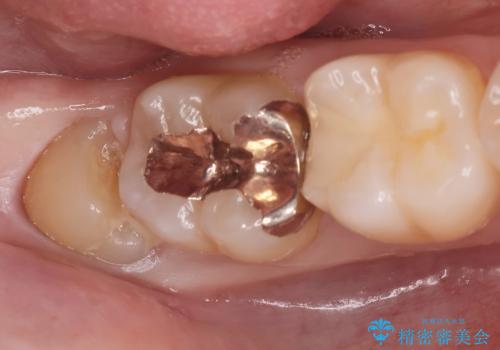

Dr. 長嶋美咲の症例写真

担当医 長嶋美咲<2025年12月23日更新>